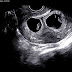

On obstetric ultrasound, the gestational sac is a dark ("anechoic") space surrounded by a white ("hyperechoic") rim.

Gestational sacs can be identified via ultrasound and are generally identified by the following 4 characteristics:

- The sac has a round or elliptical shape in longitudinal and transverse views

- it is surrounded by a white echogenic rim ("choriodecidual reaction")

- The sac is located in the uterine fundus

- The sac is not implanted on the midline, but eccentrically (to one side of the uterine cavity line).